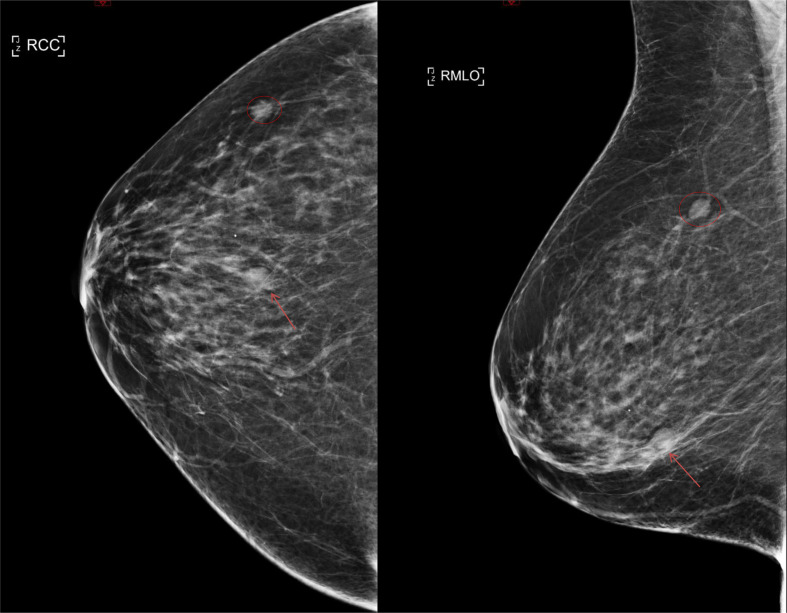

A number of COVID-19 vaccines have been approved worldwide to help tackle the pandemic. As with many vaccines, this causes a reactive axillary lymphadenopathy which can mimic potentially metastatic disease in a breast screening patient. It is therefore important to be aware of this side-effect of the vaccination when evaluating the axilla in a breast screening patient. We present a case of biopsy-proven unilateral reactive axillary lymphadenopathy in a high risk BRCA carrier following administration of the Astra Zeneca vaccine.

Abstract Image